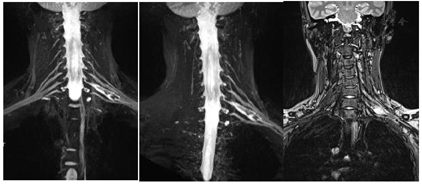

术后查体:左肘腕关节活动自如,左臂屈曲、外展可,神经感觉未见明显异常。术后肿瘤组织送病理检查,HE染色示神经鞘瘤。免疫组化结果:S100(+),SMA(-)。术后2周后未出现臂丛神经损伤症状及其他并发症,治愈出院。术后1周(图3)、1个月(图4)、半年(图5)、一年(图6)复查颈部MRI+增强及臂丛神经重建如下。

手术切除是治疗臂丛神经鞘瘤的有效方法,特别适用对于出现有神经压迫症状的患者。神经功能的保护是神经外科手术永恒的话题。对于神经肿瘤的手术更是如此,如何做到在不损伤载瘤神经的前提下完整切除肿瘤是手术中的难题。此例病例的对于神经保护的经验是:首先是合理运用神经电生理监测能为我们手术保驾护航,术中适当诱发臂丛神经电位以便实时了解神经功能情况。其次是手术技巧,暴露肿瘤时,应当是将相连的神经干一并游离,然后纵行切开平行于神经干的包膜,逐层分离包绕肿瘤的神经束,至肿瘤表面时开始剥离,避免术后出现臂丛神经损伤症状。若将肿瘤连同载瘤神经一并切除,将引起不可逆的神经损伤。在肿瘤的分离和切除过程中,神经有可能因牵拉而出现术后障碍,但这种损伤是可逆的,经过保守治疗可恢复。本案例中手术中通过上述的手术技巧,成功保留住载瘤神经并全切肿瘤,另外术后患者也并没有出现臂丛神经损伤症状。

综上所述,我们推荐对于臂丛神经鞘瘤的患者,常规行MRI-3D重建臂丛神经定位及术中应用神经电生理监测,以求最大程度避免臂丛神经损伤。